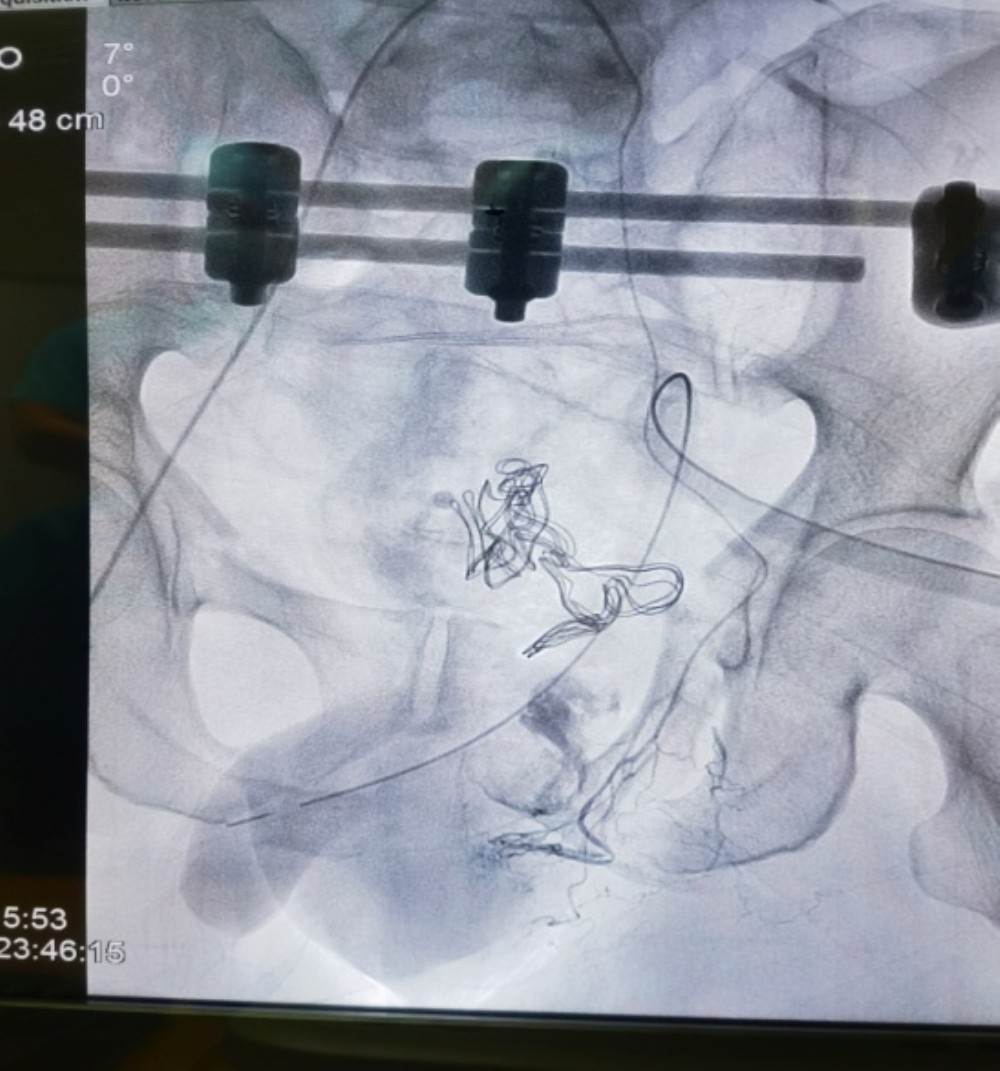

多学科“作战” 与死神较量

麻醉手术中心乌兰娜日医师为患者行全身麻醉后,普通外科吕冰副主任医师团队及创伤外科中心A区关健医师组成的手术团队迅速行剖腹探查术。术中可见,患者膀胱多处裂伤(最长可达5cm),尿道断裂、毁损严重,且盆腔内多处大量出血。手术团队快速修补膀胱并进行造漏,术中拟探查活动性出血时发现出血部位于盆腔深处,难以探及。立即请综合外科李鹏飞医师会诊,李鹏飞医师考虑为髂内动脉分支出血,为快速止血挽救患者生命需行高选择性髂内动脉分支栓塞术,遂同唐克成医师急行手术治疗。随后,我科医师成功实施骨盆骨折闭合复位外固定治疗,患者术中出血约1700ml,输同型红细胞8U、血浆790ml。术后,患者生命体征平稳,转入重症医学科继续治疗。

血管造影见髂内动脉分支破裂出血

血管栓塞术后,血管破裂出血明显减少